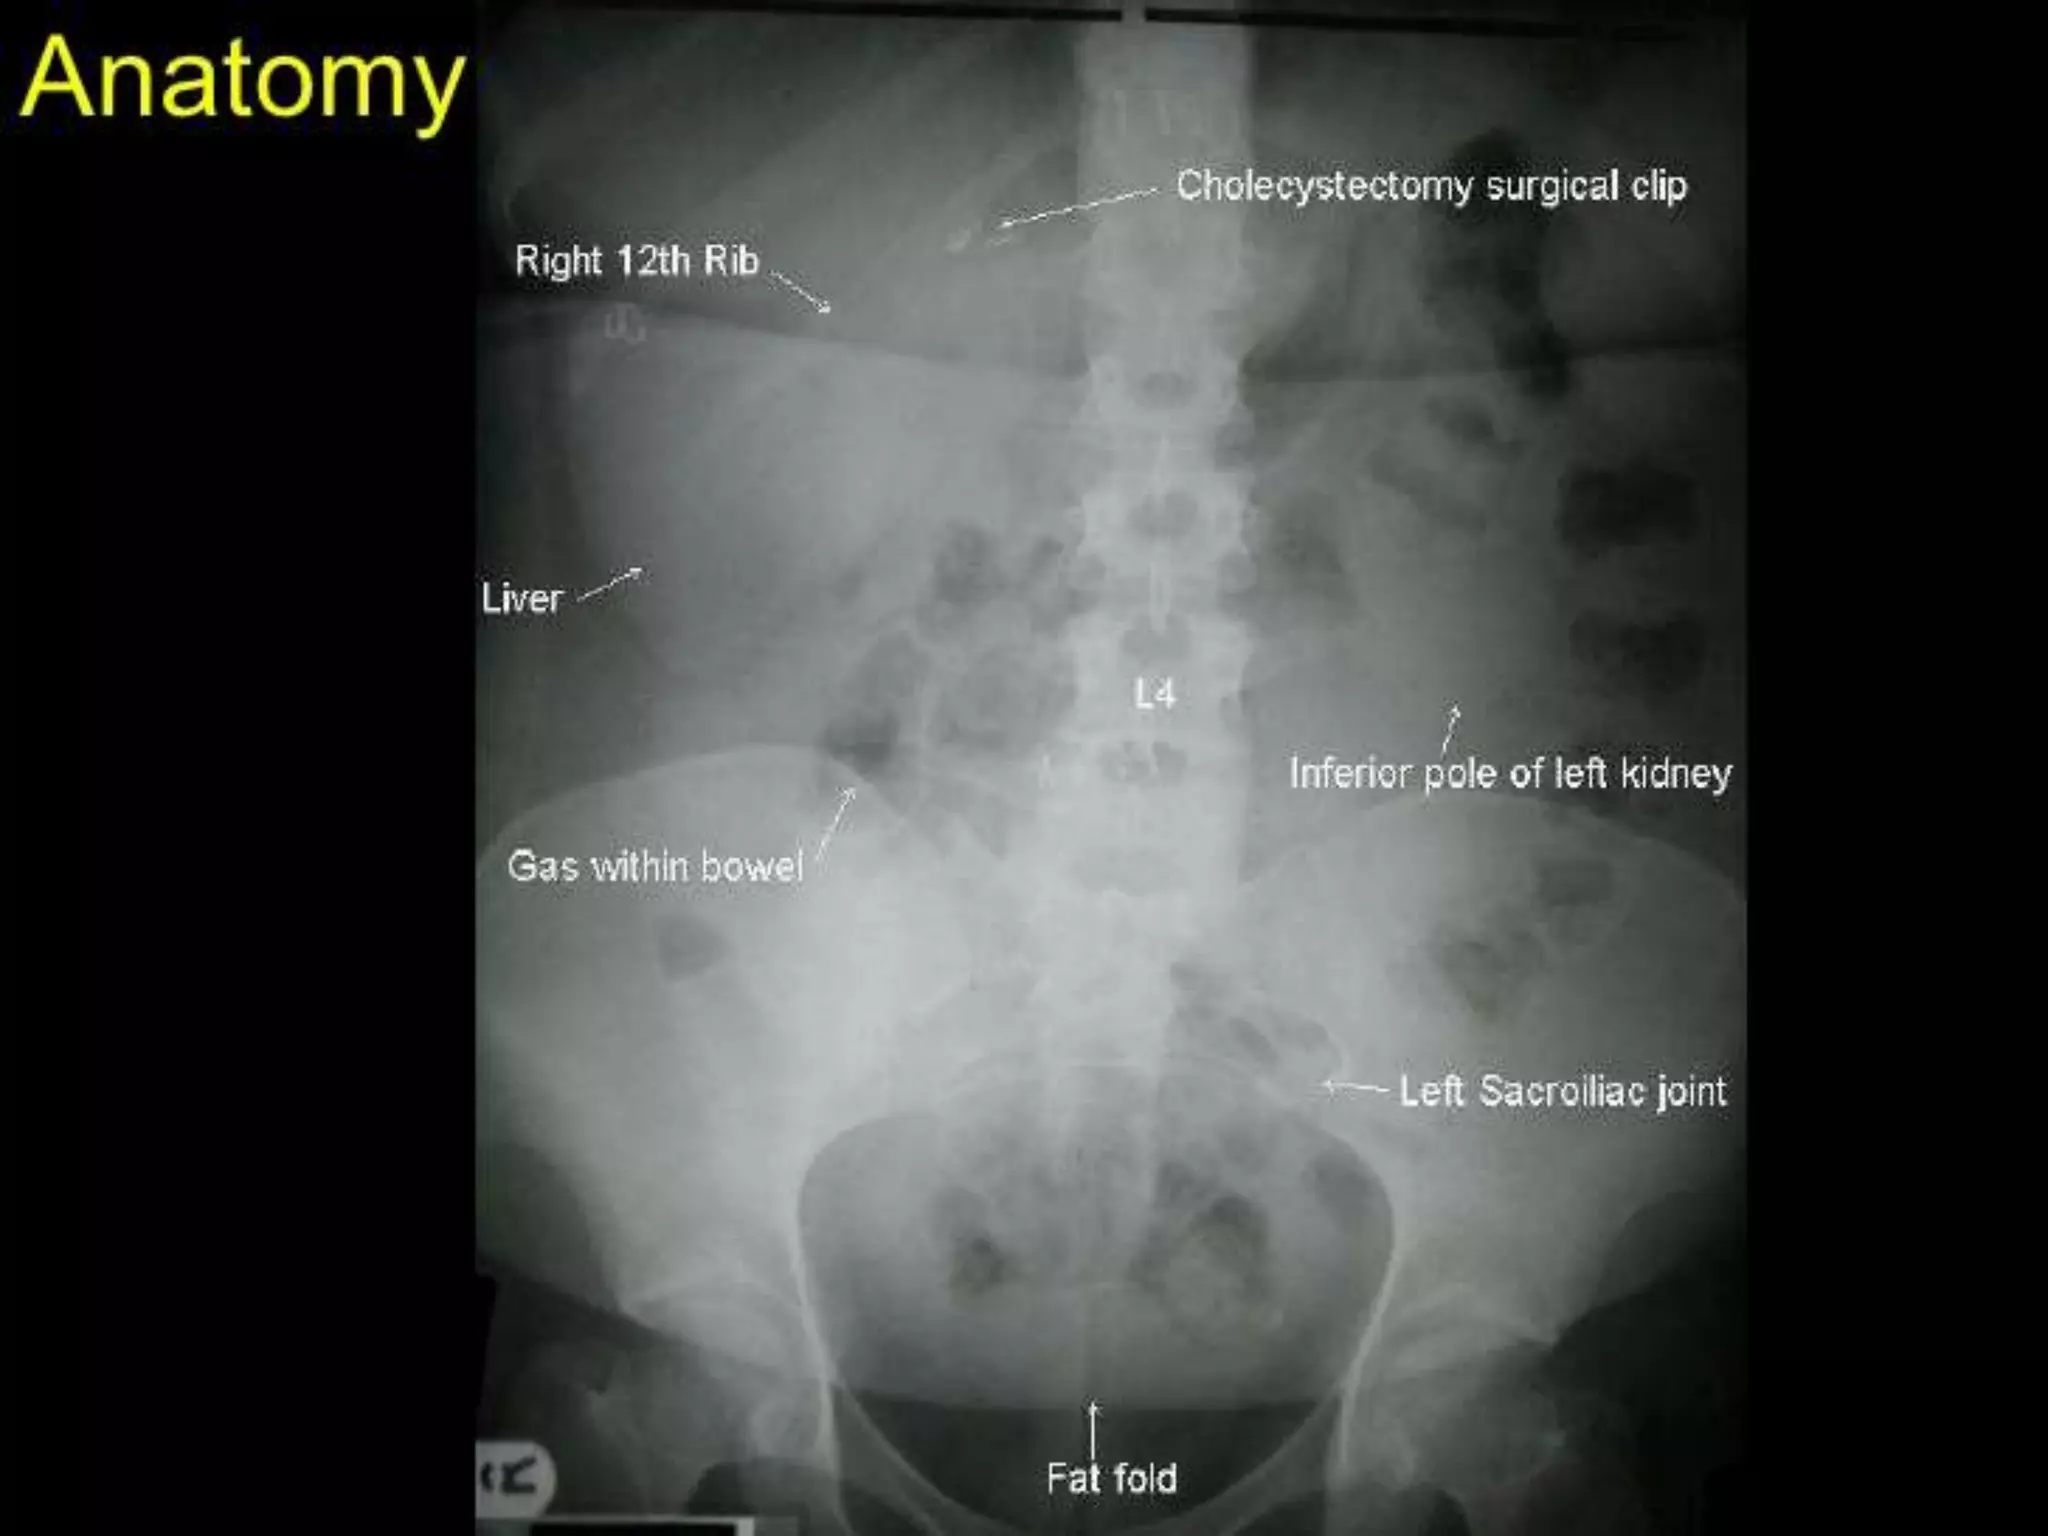

Area: supra-renal - below symphysis.

Assessment of Bones, stones, masses &

gases.

KIDNEYS: visualised if peri-renal fat.

GUT GASES: may over lap.

Change in shape & location

displaced by compression.